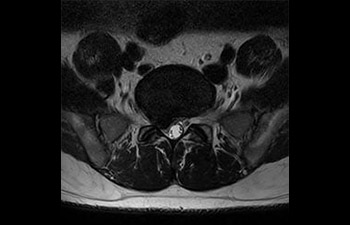

• Es una innovadora técnica de aceleración que no solo permite agilizar las secuencias, sino todo el estudio. • Implementación especial con la que las exploraciones en 2D y 3D pueden llegar a ser hasta un 50% más rápidas con una calidad de imagen prácticamente equivalente.1

• Se puede usar con todos los contrastes y con todas las regiones anatomías.